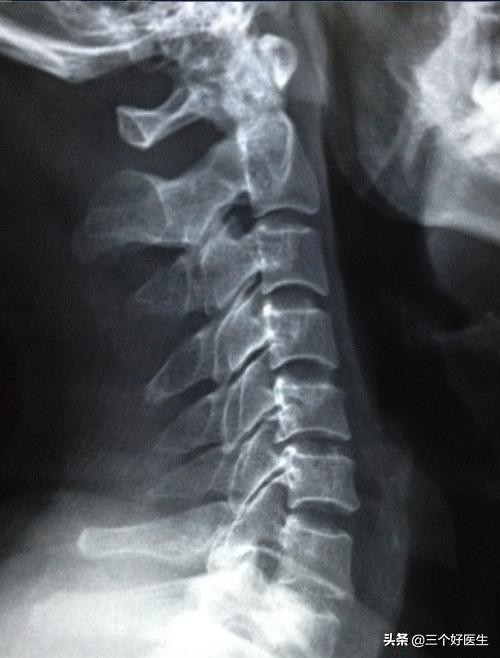

第一阶段:生理曲度正常,椎间隙正常,存在少许关节的紊乱,无明显增生。

第二阶段:生理曲度变直,后纵韧带钙化,关节开始出现增长。